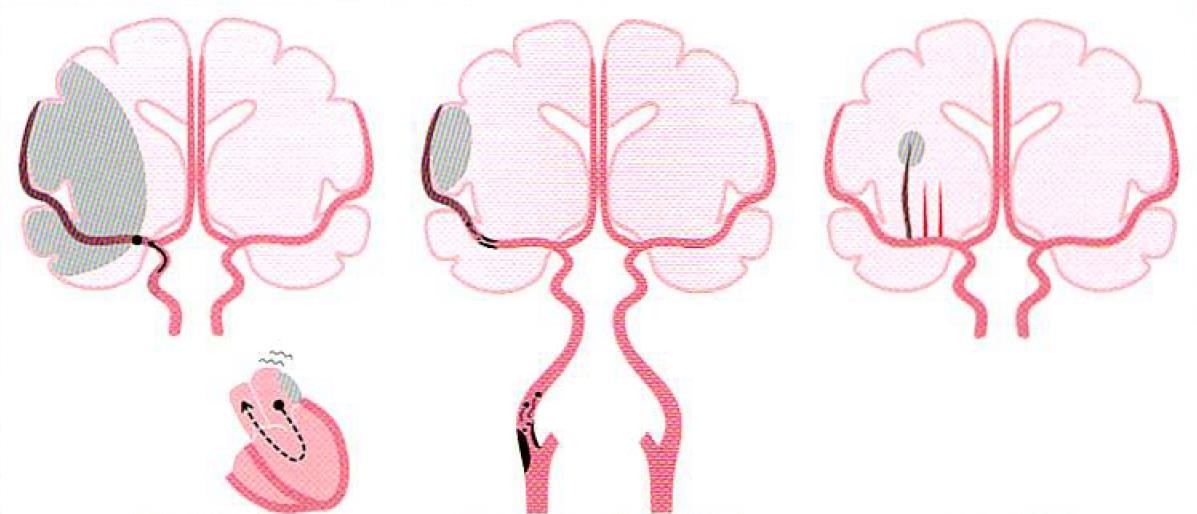

정의: 뇌경색은 뇌로 가는 혈관이 막혀서 뇌 조직에 혈액 공급이 차단되어 발생하는 뇌졸중의 일종입니다. 주로 뇌경색과 허혈성 뇌졸중으로 불립니다.

원인: 혈관 내 혈전(피떡)이나 색전(이물질)이 뇌혈관을 막아 발생합니다. 주요 원인으로는 동맥경화, 심장 질환, 당뇨병, 고혈압, 고지혈증 등이 있습니다.

4. 뇌경색 치료 방법

뇌경색의 치료는 발생 시점과 환자의 상태에 따라 달라집니다:

(1) 급성기 치료

- 혈전 용해제 투여: 혈전을 녹여 혈류를 재개통합니다. 치료는 증상 발생 후 4.5시간 이내에 시작하는 것이 효과적입니다.

- 혈관 내 시술: 혈전이 큰 경우, 혈관 내로 장비를 삽입하여 직접 제거하는 방법이 있습니다.